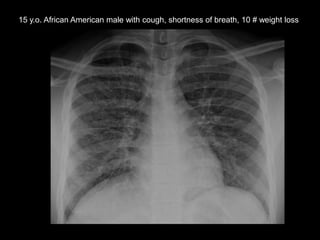

This document discusses 4 unknown pediatric radiology cases presented by Dr. Kirsten Ecklund from Boston Children's Hospital. Case 1 involves a 7 year old boy with fatigue, knee pain and swelling. Case 2 is a 15 year old African American male with cough, shortness of breath and 10 pound weight loss. Case 3 is an 8 year old boy with abdominal pain, distention and vomiting. Case 4 is an 11 year old boy with 6 months of bilateral knee pain greater on the right side.